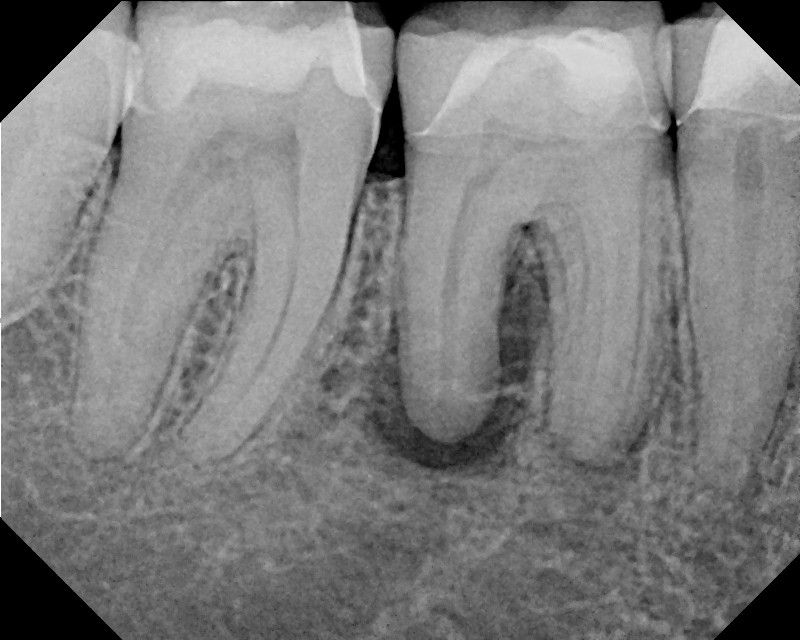

Durch Karies, undichte Füllungen oder Kronen, tief entzündete Zahnfleischtaschen oder durch Zahnverletzungen können Bakterien in das Innere des Zahnes vordringen und dort eine Entzündung auslösen. Das kann – muss aber nicht – starke Schmerzen auslösen. Die Entzündung kann sich über die Zahnwurzel hinaus in den Knochen ausbreiten und stellt dann eine Gefahr für den gesamten Körper dar. Ziel der Wurzelbehandlung ist es, die Bakterien aus dem Zahn vollständig und dauerhaft zu entfernen, damit die Entzündung ausheilen kann. Durch eine Wurzelkanalbehandlung, die nach den aktuellen Qualitätsrichtlinien mit modernster technischer Ausstattung und großer fachlicher Erfahrung durchgeführt wird, kann der Zahn mit einer hohen Erfolgsaussicht erhalten werden.

Jeder Zahn wird in seinem Inneren vom Zahnmark, der Pulpa, durchzogen. Die Pulpa setzt sich zusammen aus Blutgefäßen für die Versorgung des Zahnes mit Sauerstoff und Nährstoffen, Nervenfasern für die Sensibilität des Zahnes und aus Bindegewebe. Die Pulpa verläuft in Wurzelkanälen, die man sich aber nicht als einfache Röhren vorstellen darf, sondern als komplexes verzweigtes Hohlraumsystem. Wenn sich die Pulpa mit Bakterien infiziert, breitet sich die Entzündung in alle Bereiche des Wurzelkanalsystems aus und kann den Zahn auch an der Wurzelspitze verlassen, sodass auch der umliegende Knochen betroffen ist.

Ziel der Wurzelkanalbehandlung ist es, das Wurzelkanalsystem so zu reinigen und zu desinfizieren, dass das infizierte Gewebe restlos entfernt wird. Anschließend werden alle Hohlräume mit einer kompakten Wurzelfüllung versiegelt, damit kein Raum für erneute Entzündungsprozesse bleibt. Der Zahn wird dann bakteriendicht verschlossen und später meistens mit einer Krone oder Teilkrone aus Keramik stabilisiert, damit er nicht auseinanderbrechen kann.